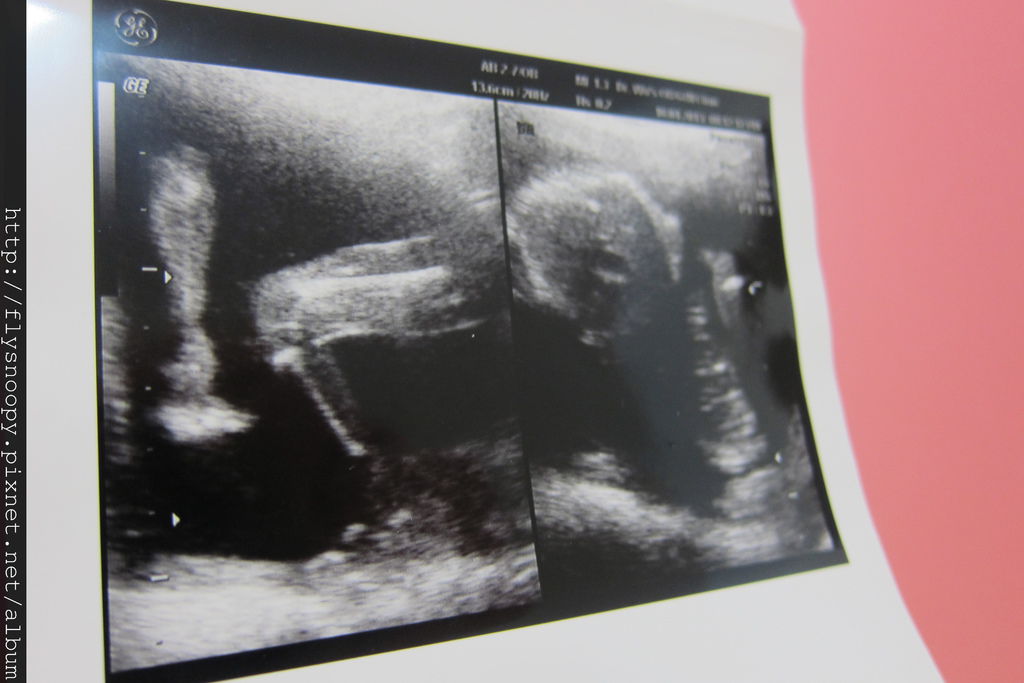

第一張照片是baby的脊椎,拍得好明顯喔,

第二張左邊是baby的腳

第三張我忘記是什麼^^"

第四張一樣是趴著,看不出來性別